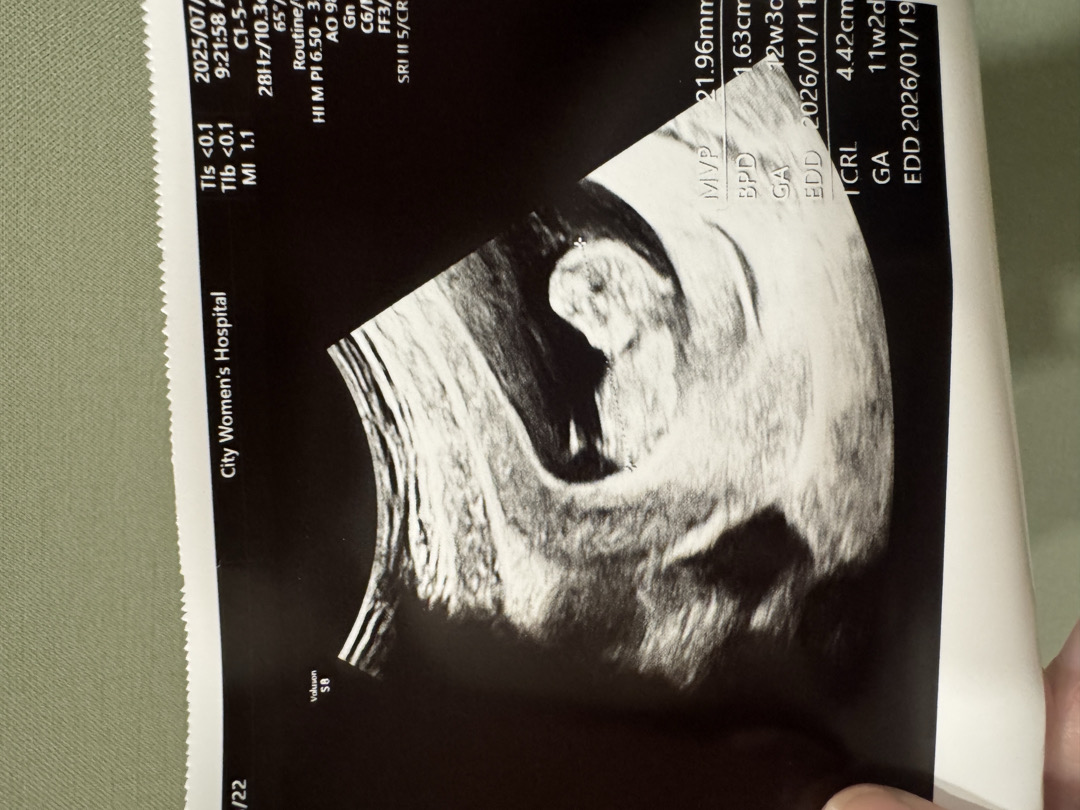

성별 뭘까요,,

성별 알수 있을까요 ? 궁금하네용

아들같아요!

왕자님에 한표요!